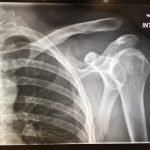

Plain films of the left shoulder showed elevation of the left clavicle above the acromion. There was an increase in the acromioclavicular (AC) and coracoclavicular (CC) distances (increased joint distances marked with red and blue arrows, respectively). A normal AC joint measures 1-3 mm whereas a normal CC distance measures 11-13 mm.1 The injury was classified as a Rockwood type III AC joint separation.